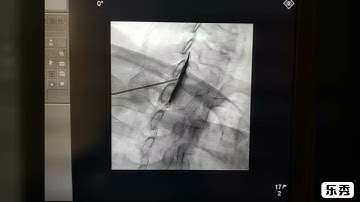

C-Arm Guided Cervical Epidural Steroid Injection: Contralateral Oblique Technique